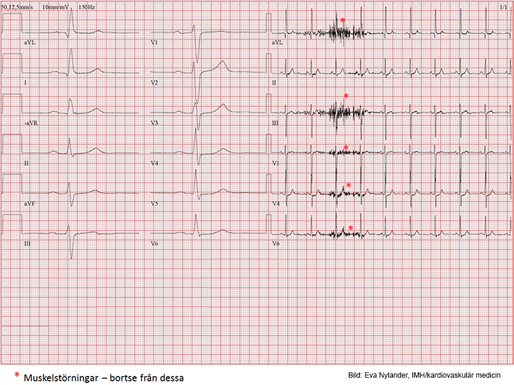

Vad kan du utläsa av detta?

I vila inga ST- T- förändringar. Under arbete ses en successivt ökande ST- sänkning över vänster kammare (tyder på koronar insufficiens). Sänkningen är platåformad och uppgår till mer än 2 mm (0.2 mV) i V5 och V6 på högsta belastningen (men ses ju även under II och aVF). Efter arbete går ST- sänkningen i regress men 6 minuter efter arbetet ses en accentuerad formförändring och T- negativitet i vänstersidiga bröstavledningar. EKG-reaktionen är patologisk och är förenlig med coronarinsufficiens.